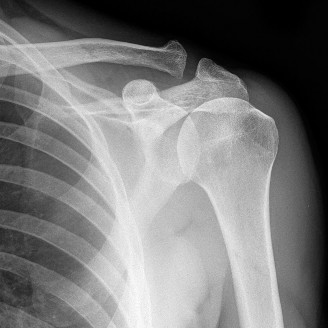

Plain Radiography Evaluation

Standard orthogonal anteroposterior and lateral radiographic views of the left elbow were obtained in the clinic. The interpretation of these radiographs is critical in differentiating primary adhesive capsulitis from post-traumatic arthrofibrosis or degenerative joint disease.

The radiographs revealed no evidence of acute fracture, chronic non-union, malunion, dislocation, or subluxation. The ulnohumeral and radiocapitellar joint spaces were well-maintained without evidence of asymmetrical narrowing, subchondral sclerosis, or significant marginal osteophyte formation. Furthermore, there were no visible intra-articular loose bodies, and no evidence of heterotopic ossification within the anterior or posterior soft tissue envelopes. The absence of these osseous abnormalities strongly supported a purely soft-tissue driven pathology, pointing directly toward intrinsic capsular contracture.